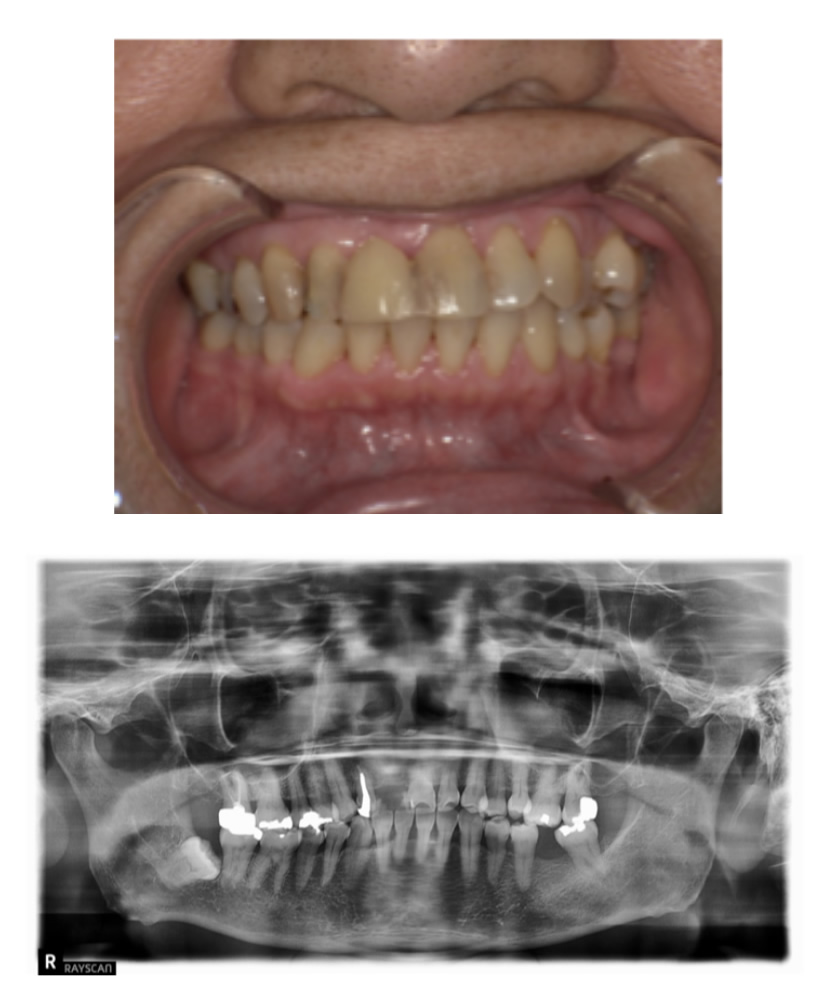

歯の根の状態が悪いためインプラントにしたい

Before

After

| 治療内容 | 前歯の見た目が悪く、歯の根の状態も悪いのでインプラントにしたい。 |

| 患者様 | 50代女性 |

| 主訴 | 歯の根の状態が悪いためインプラントにしたい |

| 治療期間(目安) | 5ヶ月 |

| 治療費(税込:目安) | ¥2,702,700 (土台:5本、被せ物:7本) |

| リスク | 術後に多少の痛みや腫れが出ることがある。歯肉退縮がおきると、歯と歯肉の間に隙間が生じることがあります。 |